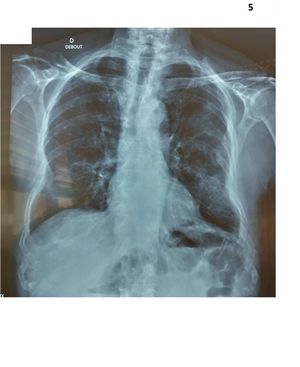

Is this a healthy or unhealthy person?

Unhealthy?

Unhealthy

Yes definitely; but what’s the diagnosis?